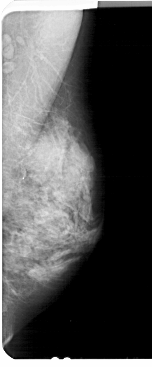

A_1926_1.LEFT_MLO

LEFT_MLO LINES 5326 PIXELS_PER_LINE 2341 BITS_PER_PIXEL 12 RESOLUTION 43.5 OVERLAY

FILE: A_1926_1.LEFT_MLO.OVERLAY

TOTAL_ABNORMALITIES 1

ABNORMALITY 1

LESION_TYPE CALCIFICATION TYPE PLEOMORPHIC DISTRIBUTION CLUSTERED

ASSESSMENT 4

SUBTLETY 2

PATHOLOGY BENIGN

TOTAL_OUTLINES 1

BOUNDARY